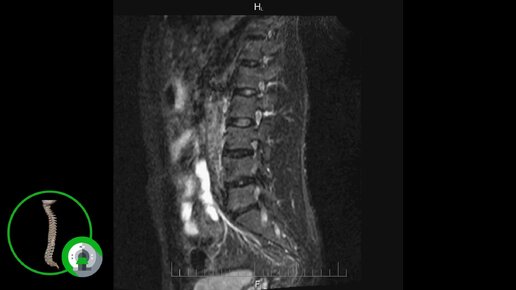

Что покажет МРТ поясничного-крестцового отдела позвоночника (видео)